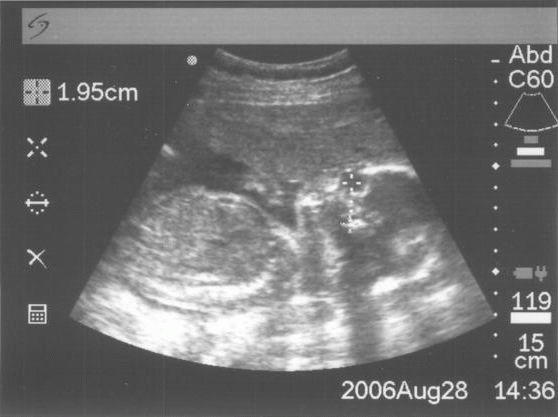

Gabi 12+5